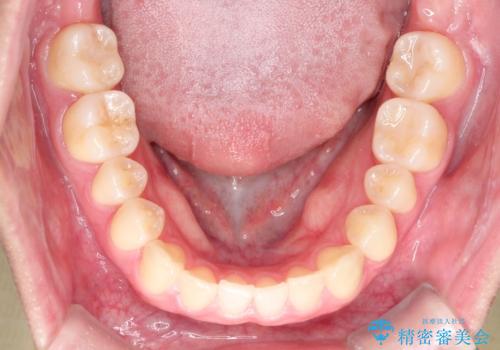

- 前歯のガタツキが気になるとのことで来院されました。

ワイヤー矯正とインビザライン矯正を併用することによって、治療期間の短縮と、より良い仕上がりを目指す治療を選択することとしました。

インビザライン(アライナー)矯正とワイヤー矯正のそれぞれの利点を生かした治療を行い、綺麗な歯並びになりました。